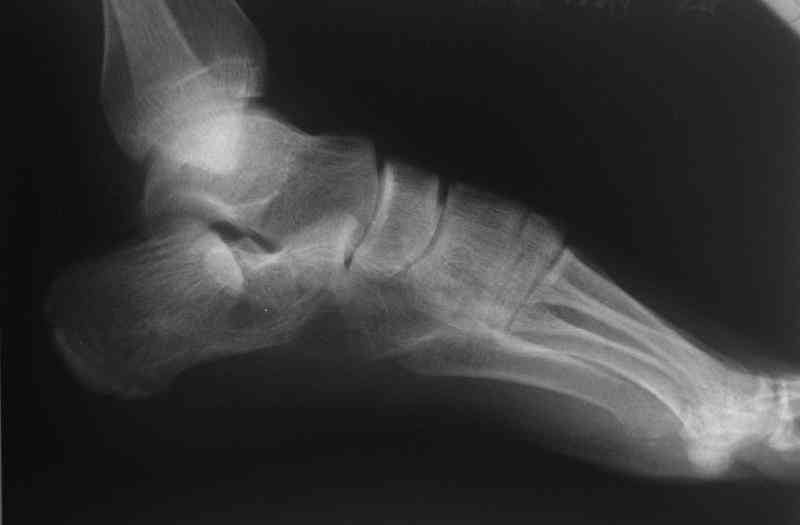

Re: Перелом пяточной кости

Какой предпочитаете доступ? Нет ли показательных рентгенснимков?

Открытый и закрытый способы лечения.